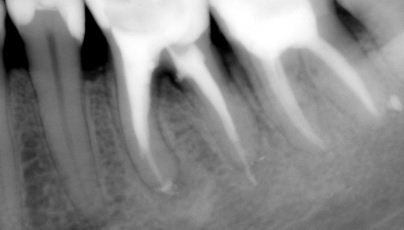

Reendo dolnej szóstki.

Wykonany zabieg resekcji wierzcchołka nie pomógł w ustąpieniu obajawów zapalnych. Skuteczne okazało sie dopiero reendo.